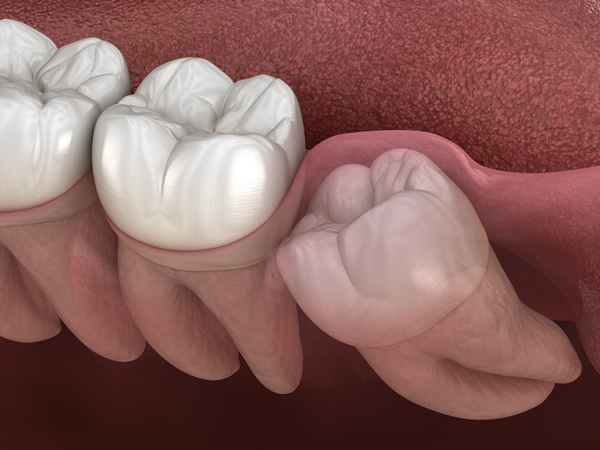

もちろん、斜めに生えている、痛みがある、腫れている場合などは、抜歯するのが最善の選択です。抜歯が難しい場合、一部の歯科医院では大学病院などに依頼することもありますが、当院ではさまざまなケースに対応しているため、ご安心ください。

親知らずの周りには、重要な血管や神経が通っています。抜歯の際には、それらを傷つけないよう細心の注意が必要になります。

親知らずに生えている歯が押されて、結果歯並びが悪くなってしまうことがあります。これはケースバイケースのためすべての親知らずが悪影響になるかは、一概には言えません。気になる方は、ご来院の上ご相談ください。レントゲンなどで、歯並びに影響があるかを調べることができます。